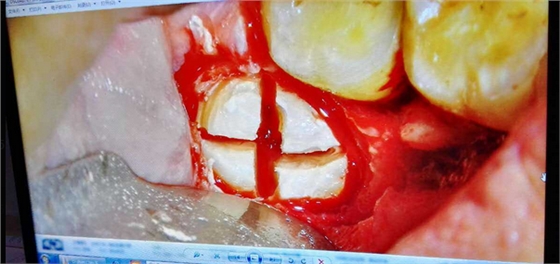

病例:患者男性47歲

右下8骨埋伏并且黏連;從根分叉處通過;有彈性;術(shù)中看到神經(jīng)束

實(shí)在找不到;近中牙冠沒去干凈

像這種不切除的牙冠,以后吸收的可能性不是很大,但有排除的可能性,自己自行排出,要是牙根的話吸收的可能性比較大

像這種沒有癥狀的殘留牙體組織不用去除可以吧

加了負(fù)腎

出血還可以,不是很多